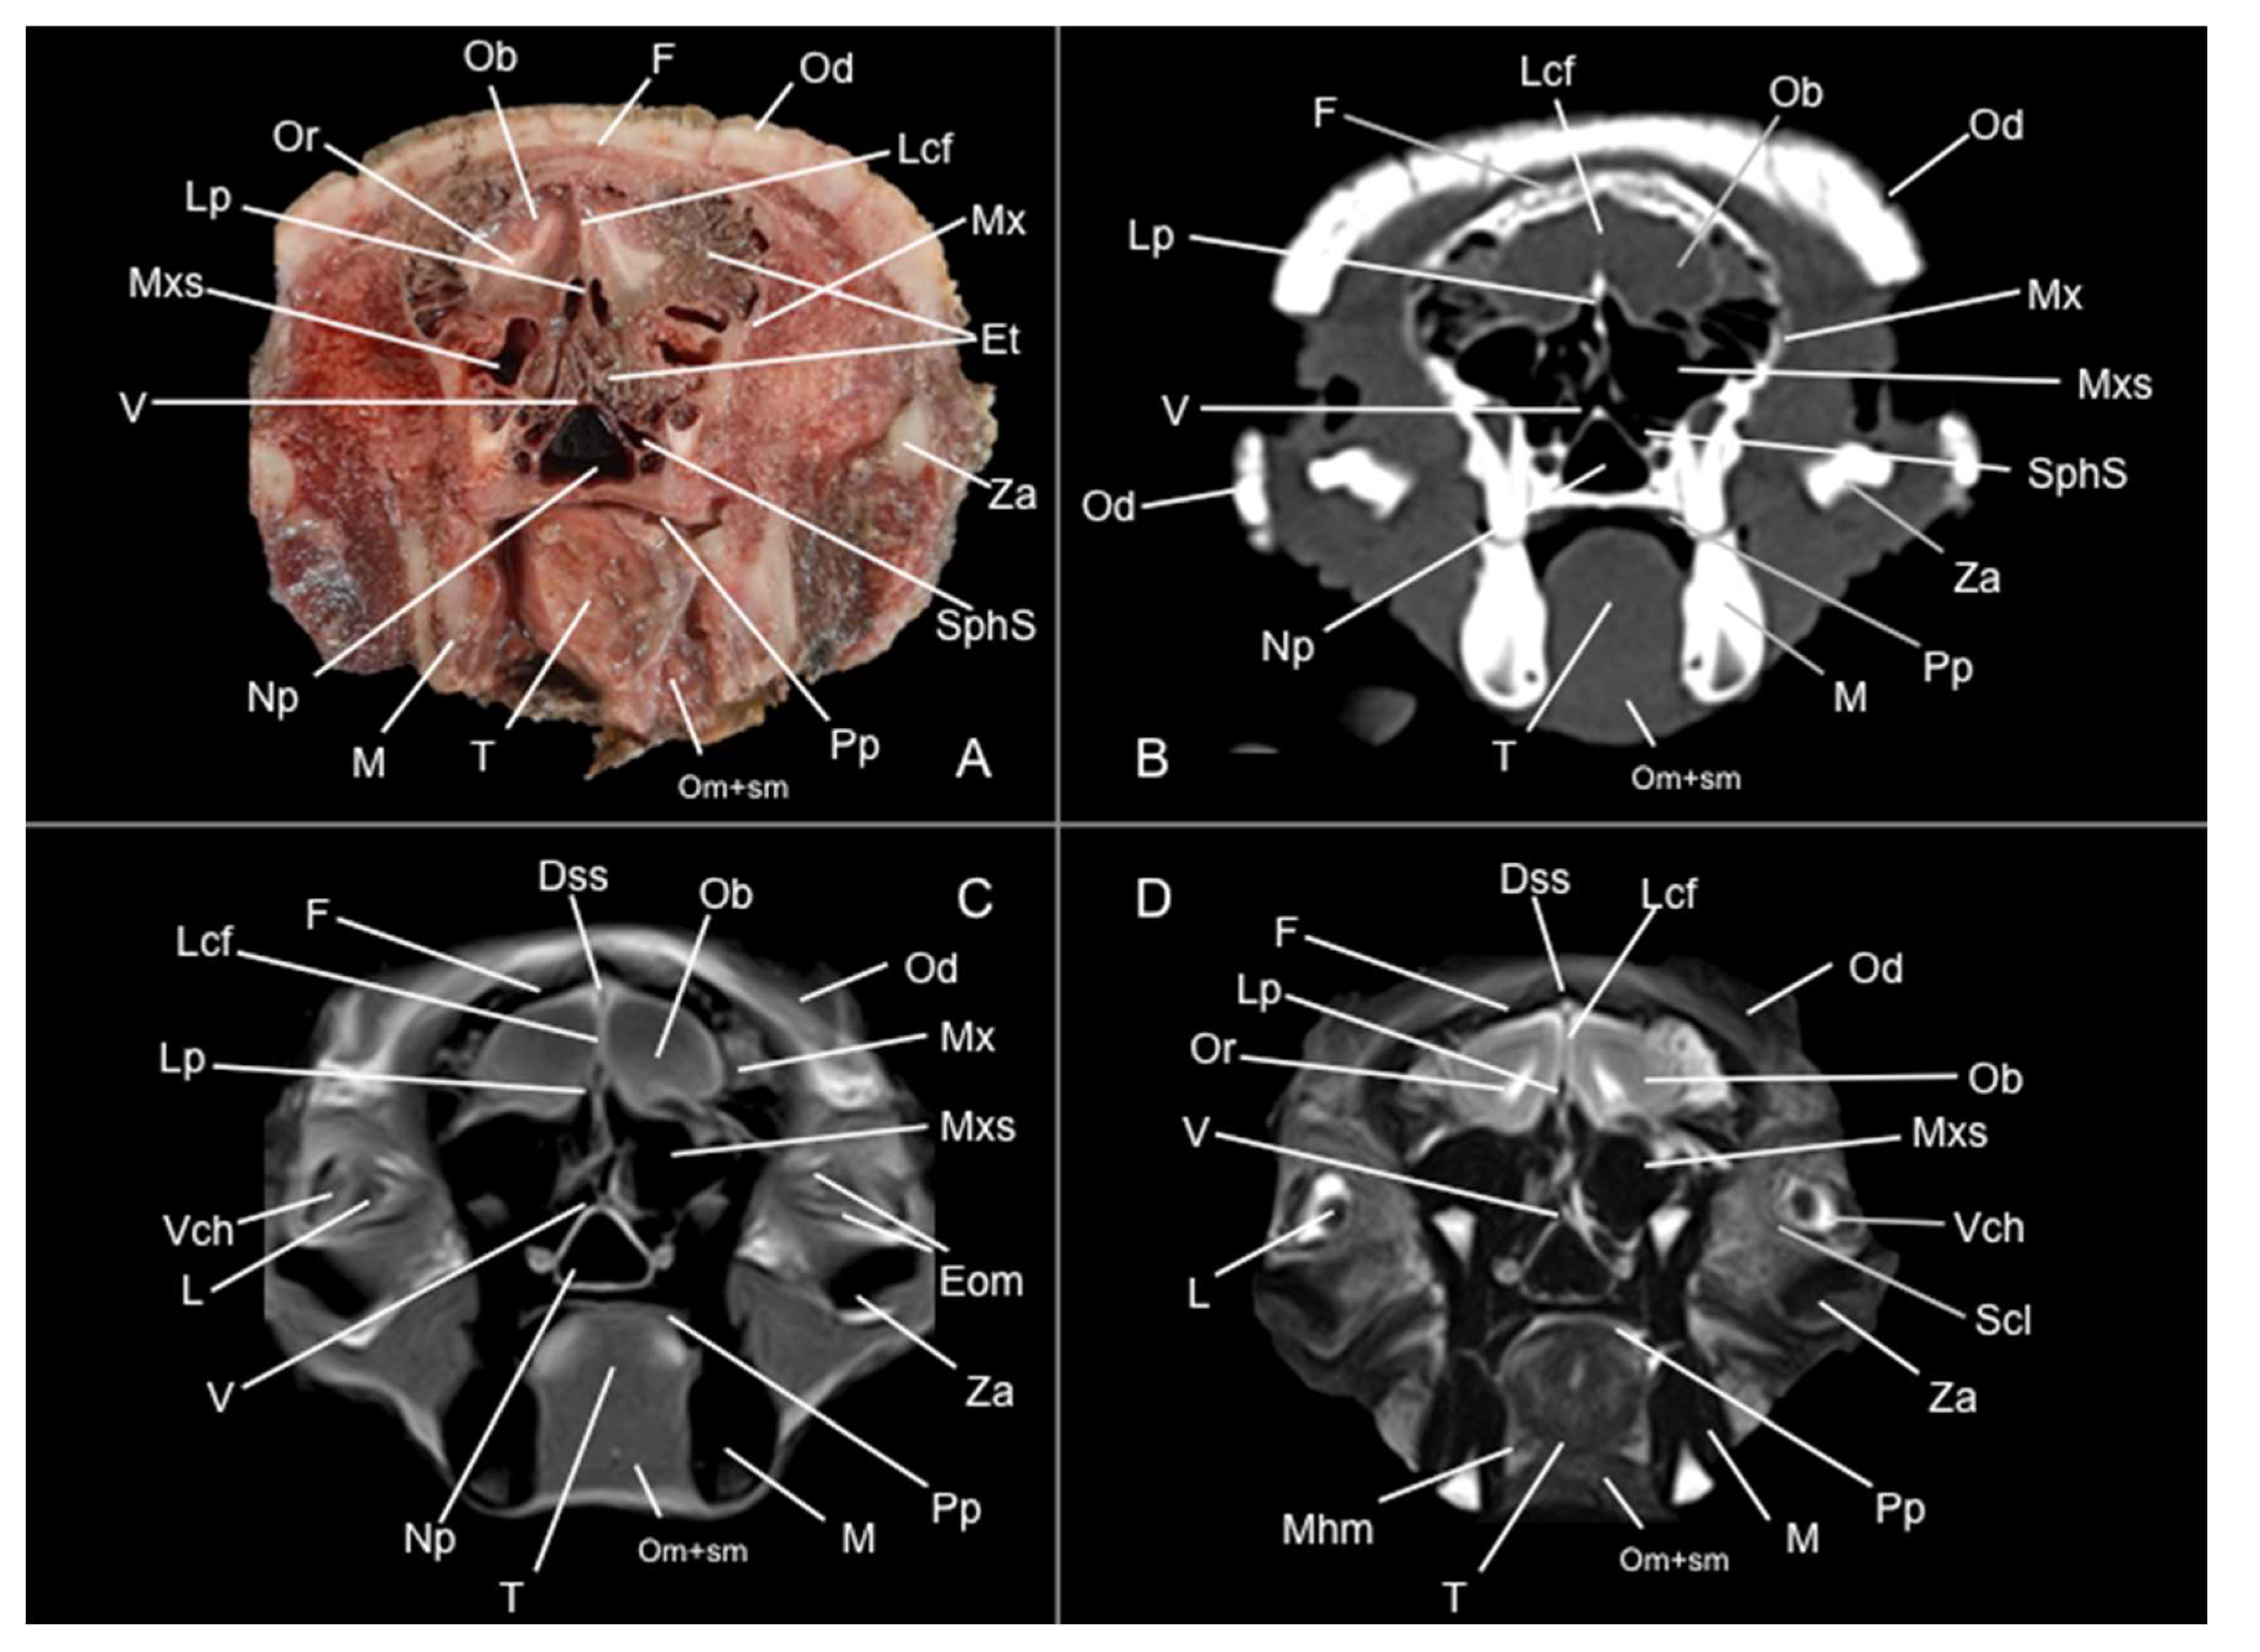

3.1. Anatomical Sections

3.2. Computed Tomography Study

3.3. Magnetic Resonance Imaging (MRI)